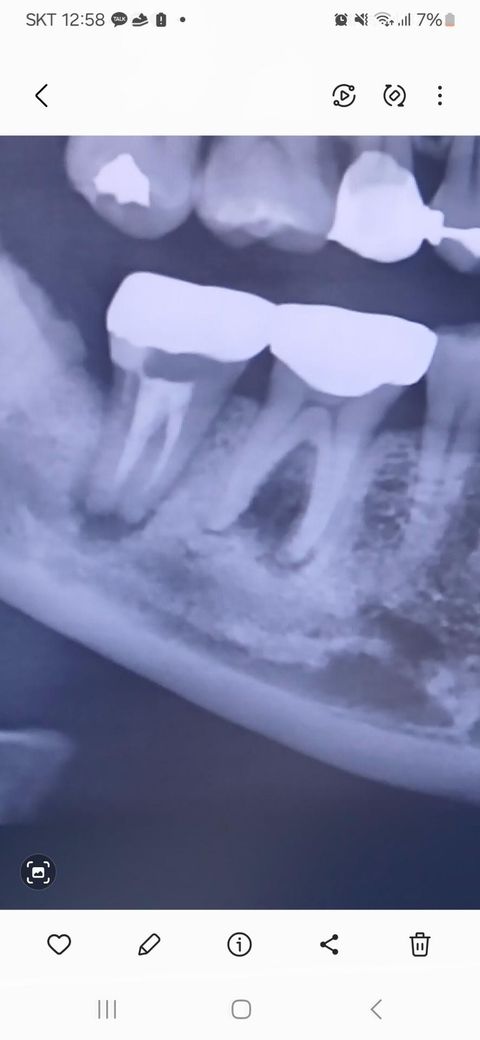

치과 엑스레이 염증 정도 궁금합니다.

염증 있는데 치아 살릴 수 있을까요

치과에서는 심각하다는데 통증은 아직 없고

자고 일어나면 염증이 차서 잇몸이 살짝 붓고

누르면 염증이 나와요 ㅠㅠ

만성농양의 상태로 두 치아 다 (재)신경치료해줘도 살리기 쉽지 않습니다 만성이니 통증은 없어도 뼈가 많이 녹았습니다

고름이 밖으로 배출되고있기 때문에 통증이 없는 것이고, 만약 고름이 잇몸안에 갇혀있다면 심하게 붓고 많이 아플 것입니다. 단 1~2년이라도 더 사용하기 위해 최선을 다하고 싶다면 신경치료를 해볼 수 있겠지만, 고생은 고생대로 하고 돈은 돈대로 냈는데 결과가 좋지 못하면 좋은 소리를 못듣기 때문에 대부분의 치과에서 발치권유를 할 것 같습니다. 가망이 없다고 판단이 되면 빨리 발치해서 임플란트를 준비 하는 것이 뼈손실을 줄일 수 있는 방법입니다. 뒷치아에도 염증이 있고, 사진에 나온 부분만 봤을 땐 앞치아는 멀쩡하기 때문에 괜히 앞뒤치아를 묶어 씌우는 방식보다는 한개씩 임플란트를 하는게 더 좋을 것입니다. 당장 임플란트 계획이 없고, 본인치아를 좀 더 써보고 싶다면 염증을 짜내고 항생소염제를 처방받아 드시면 잠깐 가라앉힐 수 있으나 다시 염증이 반복적으로 생길 것이고, 염증으로 인해 뼈는 점점 없어질 것입니다.